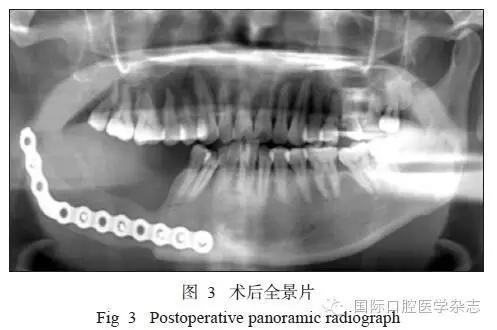

患者術(shù)后切口愈合良好,牙無(wú)松動(dòng),咬合關(guān)系良好。術(shù)后復(fù)查顯示傷口愈合良好,骨斷端生長(zhǎng)良好(圖3)。